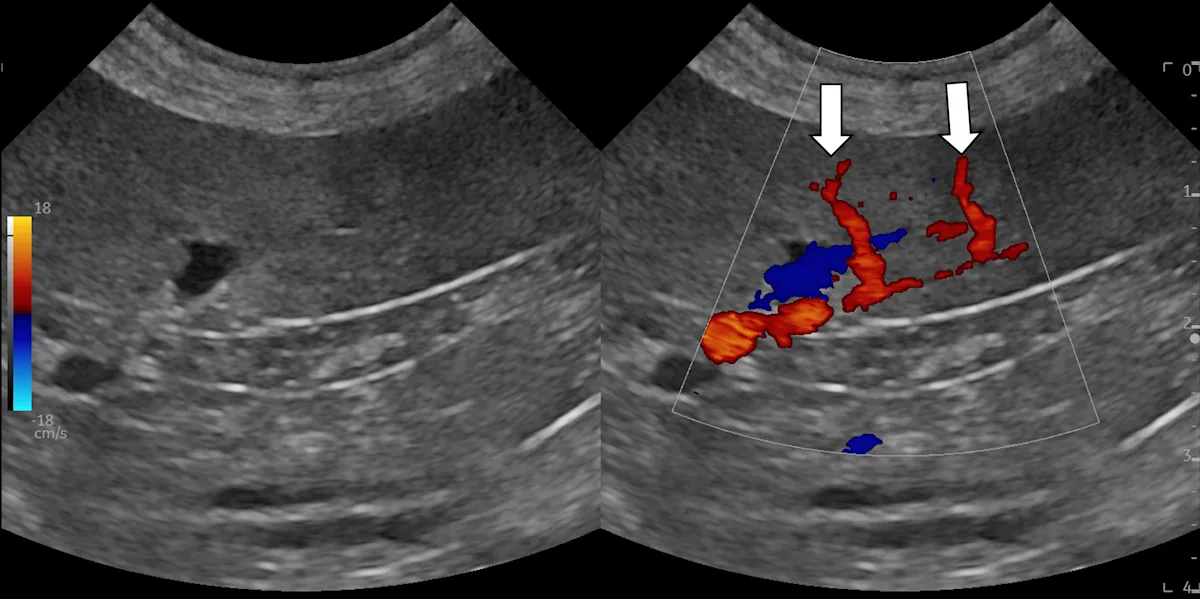

Interrogate the target and adjacent structures with gentle fanning/sweeping and rocking/sliding of the transducer in both planes. Attempt to identify the ideal window and travel path that will allow the needle to pass through the skin and directly into the lesion of interest while only passing through the peritoneal or retroperitoneal space. Avoid vessels, other organs, and separate body regions/cavities. If available, interrogate the lesion and surrounding area with color or power Doppler (see Video) to help identify vessels that may not be visible with brightness mode (B-mode) alone.

Color Doppler identifies 2 splenic arteries (arrows) extending toward the periphery. These vessels were not easily seen on B-mode and may have been punctured if sampling was performed in this area.